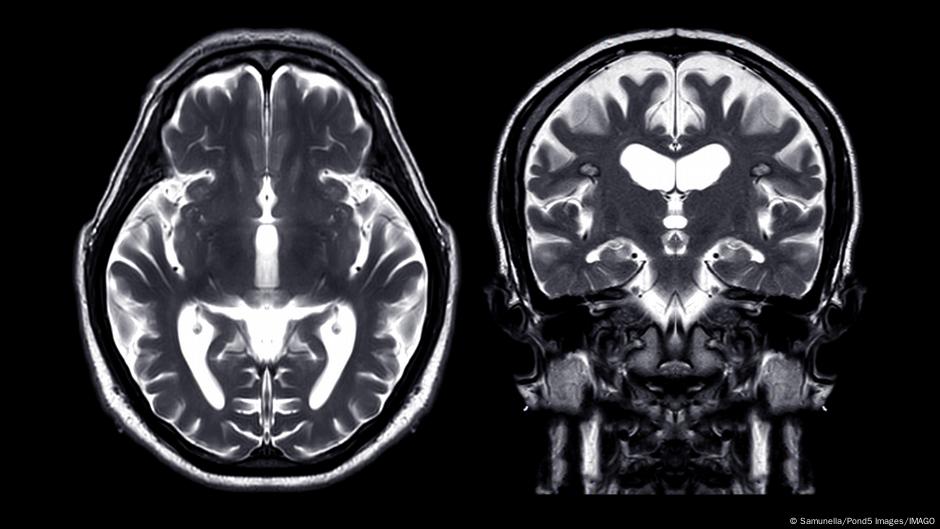

الارتجاجات الدماغية شائعة بشكل خاص في الرياضة، وغالبًا لا يُؤخذ الأمر على محمل الجد مع أن مثل هذه الإصابة الدماغية الرضّية يمكن أن تكون لها عواقب وخيمة.